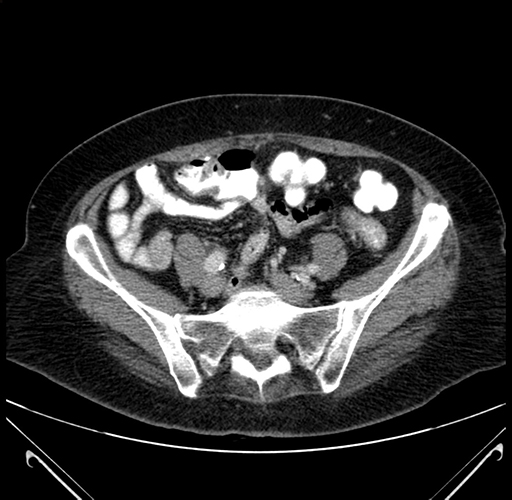

Axial Venous